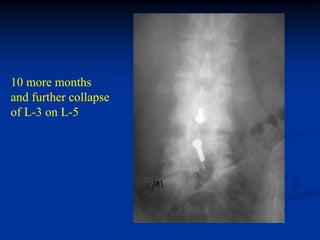

37 year male with chordoma in body of L-4

CT scan myelogram with block at L-4

Myelogram showing block

at the L-4 level

Post op x-ray following

removal of L-4 body

and recon with fibular

strut from L-3 to L-5

Lateral view of fibular

strut reconstruction

8 mos later with

collapse of L-3 on L-5

10 more months

and further collapse

of L-3 on L-5

Sagittal T-1 MRI showing collapse and kinked dural sac